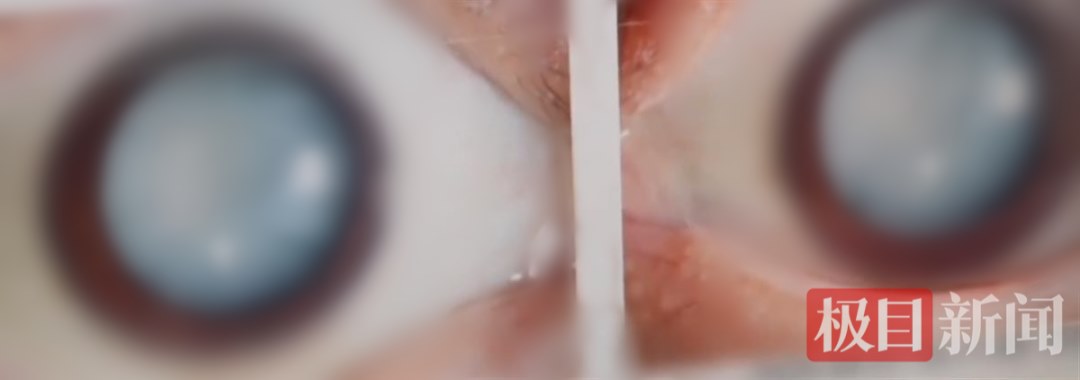

在大众的普遍认知里,白内障往往是50岁以上人群的“专利”,然而,近日,25岁的小吴一觉醒来却发现眼睛看不见了,来医院检查时,其双眼瞳孔中央已经全白,被确诊为“代谢性白内障”,经详细了解后,医生判断,小吴之所以如此年轻便患上白内障,与其平时喜爱高糖、高油、高热量的饮食习惯密切相关。小吴今年25岁,平时就喜欢高糖、高油、高热量饮食,每天至少两瓶饮料,火锅也是“家常便饭”。zui近,他一觉起来发现,自己的左眼居然看不清了,之后没过两天右眼也看不清了?!把劬σ裁挥惺苌耍褪且痪跣牙春蠓⑾盅劬ν蝗豢床患?,心里感觉非常害怕?!被叵肫鹱约夯忌习啄谡系木?,小吴至今仍感到难以置信。为此,家人赶紧带其前往武汉大学附属爱尔眼科医院就诊。该院白内障与老视专科孙明副主任医师为小吴进行了详细检查,她发现,小吴的白内障情况极为严重,晶状体几乎完全浑浊,从外观上看,双眼毫无神采,瞳孔中央一片雪白。“双眼的晶状体几乎完全是浑浊的。即使在肉眼下,我们都看到他的双眼是无神的,瞳孔中央完全是白的?!彼锩鞲敝魅我绞Ρ硎?。